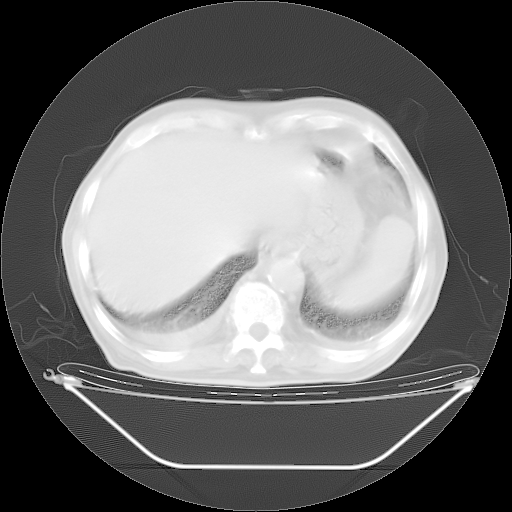

今天复查肺部CT,发现双肺广泛磨玻璃样改变。所以我把3月19日和5月9日相隔50天的肺部CT上传。请大家会诊。

5月9日肺部CT(在4月27日齐鲁医院肺部CT描述部分肺组织磨玻璃样改变,12天后肺组织广泛磨玻璃样改变)